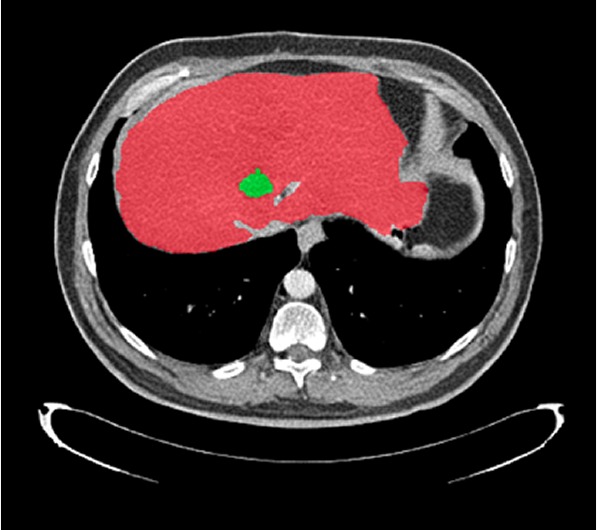

| Annotation & segmentation |

Performs precise annotation and segmentation of medical imaging data using advanced tools and expert teams. |

- Comprehensive AI Annotation Services: Leverage both 2D and 3D annotation across imaging modalities.

- 3D Medical Image Segmentation.